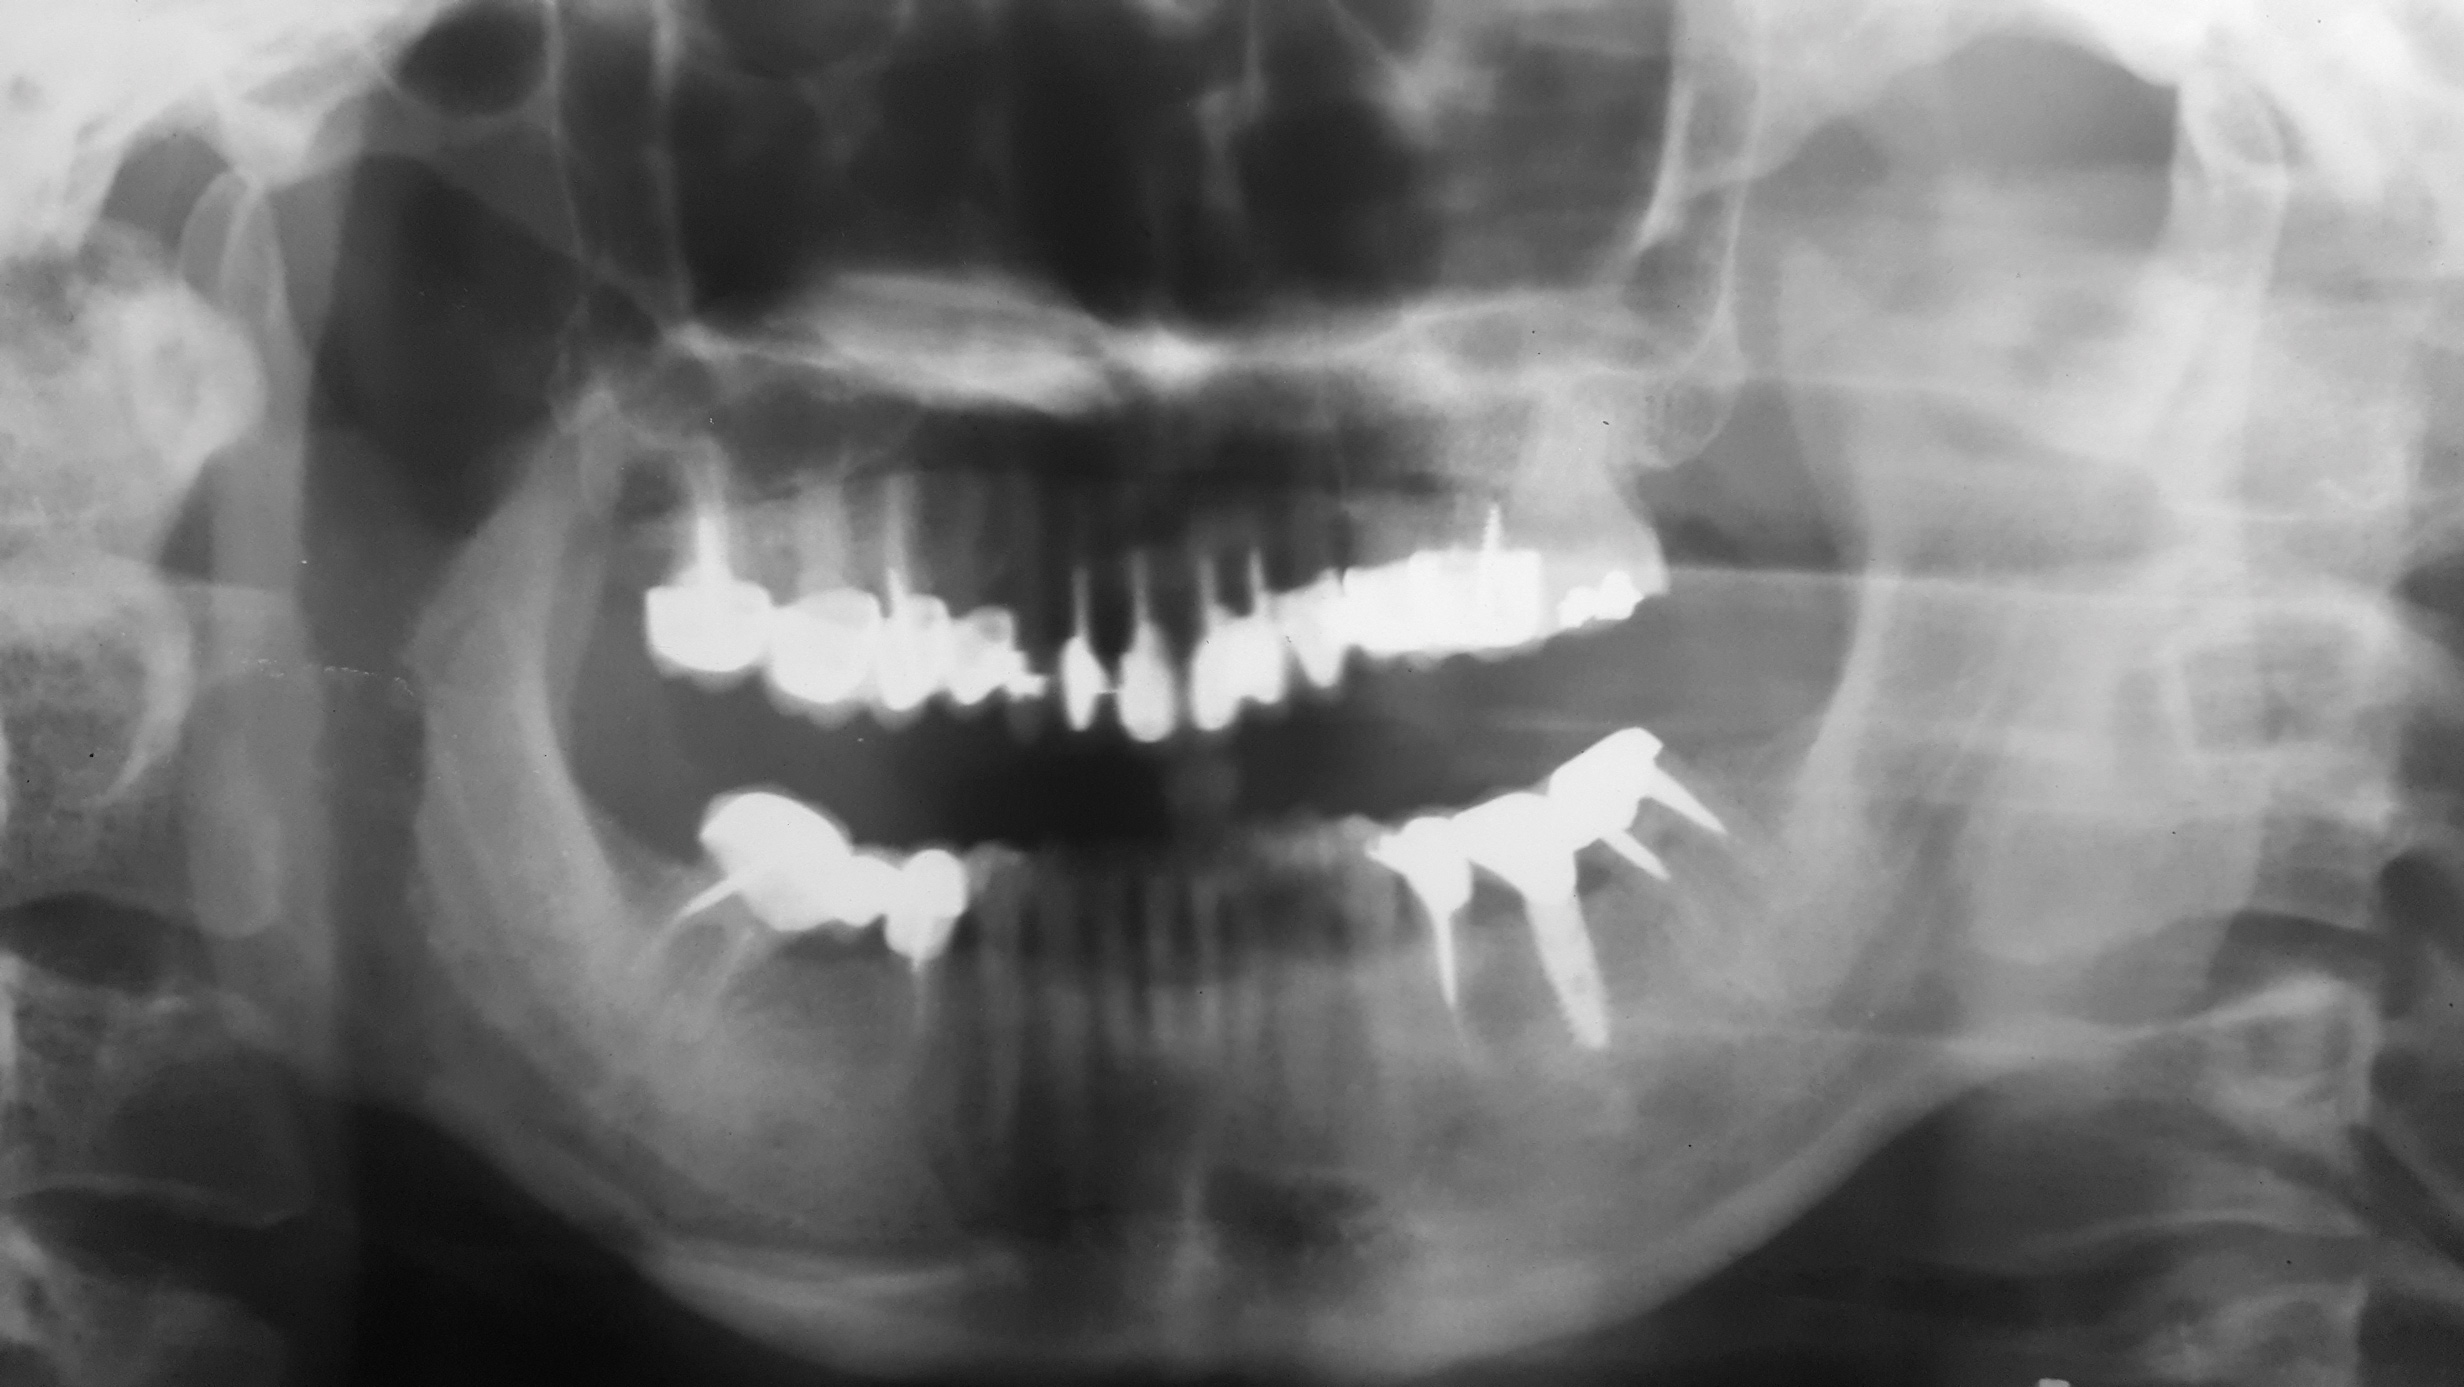

Clinical examination revealed an acute nasolabial angle, a protrusive lateral profile, and a marked short, square face (Figure 1 through Figure 3). Facial esthetics were dominated by a short LAFH with a UAFH/LAFH ratio of 54%/46% (Figure 3). Intraoral examination demonstrated bilateral class II canine and molar relationships, a 10 mm overjet and 3 mm overbite, and a deep curve of Spee of the lower dentition (Figure 4 through Figure 6). Most of her upper teeth and lower posterior teeth were crowned, with the exceptions being the upper right canine (No. 6) and upper left second molar (No. 15). Her lower right second premolar to second molar (Nos. 29 through 31) were restored with a prosthetic bridge, and her lower left second premolar (No. 20) and second molar (No. 18) were restored with crowns. Additionally, she had a dental implant in the lower left first molar (No. 19) position (Figure 7). Her upper anterior crowns had unpleasant tooth proportion, morphology, and shade.

From radiographic examination, tooth No. 18 was found to have a poor prognosis due to furcation bone loss. The cephalometric x-ray showed a skeletal class II relationship, a reduced mandibular plane angle, flared upper incisors, a deep bite, and significant overjet (Figure 6). The panoramic radiograph confirmed many restorations and that No. 19 was a dental implant (Figure 7). There were no symptoms of temporomandibular joint disorder.

Fig 7. Panoramic x-ray before treatment.

Figure 7